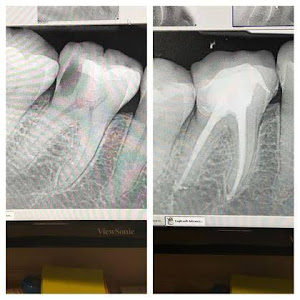

Welcome to our gallery

See how our company transforms ideas into reality. This gallery is a visual testament to our work and achievements.